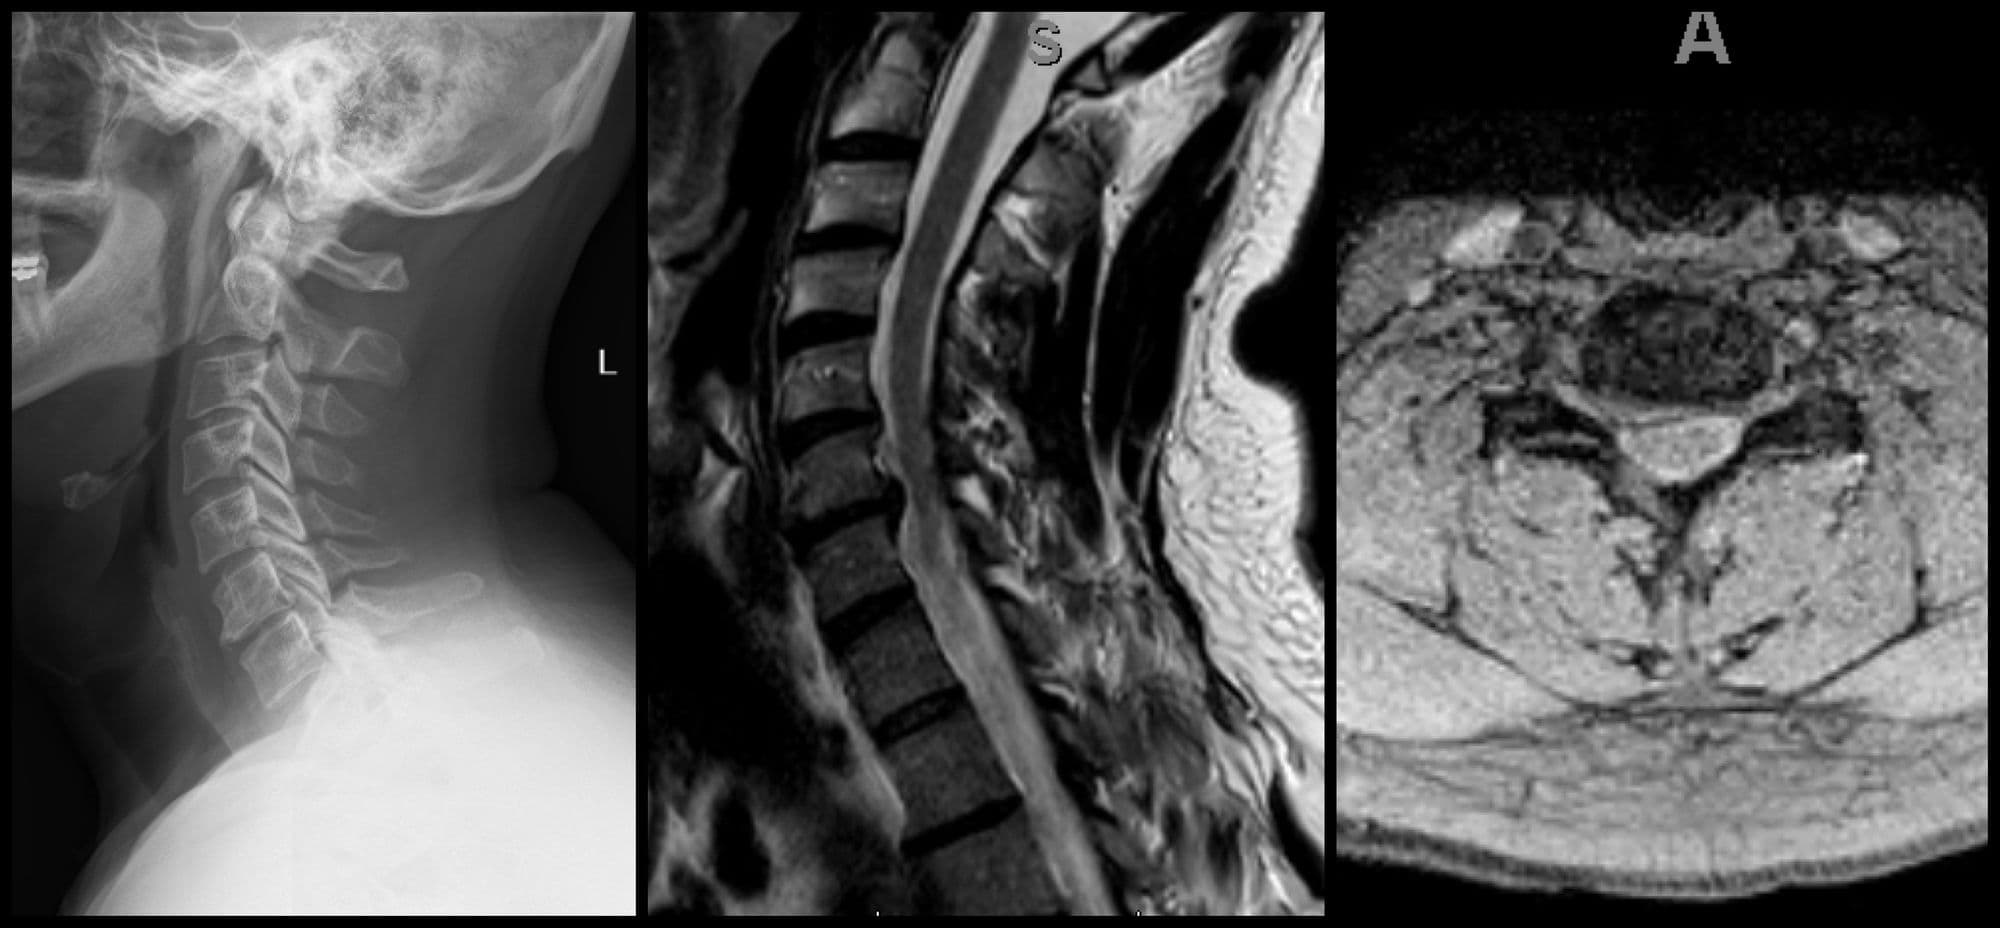

Cervical Disc Replacement

Darrel Brodke